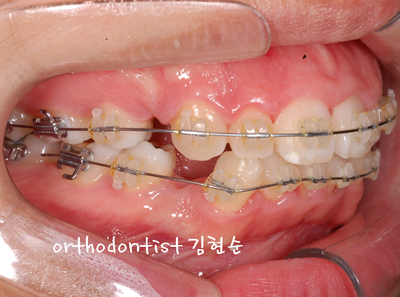

Chief Complaint

Treatment plan.